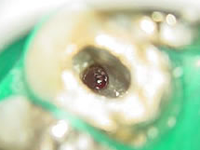

真ん中から穴をあけて治療を行うべきです。右の写真がそのやり方です。